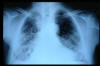

TBC pulmonar antigua